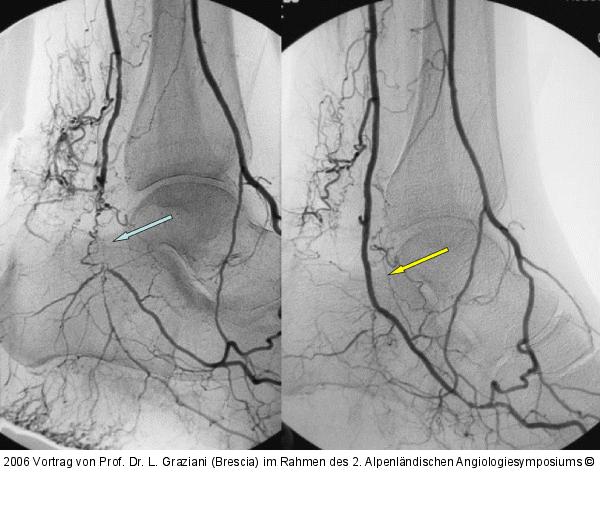

Abbildung 80: Arteria dorsalis pedis - Katheterisation

Arteria dorsalis pedis - Katheterisation